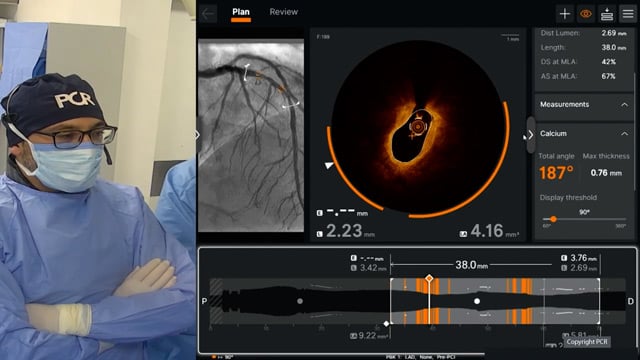

Seeing is believing: OCT-guided calcium modification in complex PCI

10 Dec 2025 – From GulfPCR-GIM 2025

Explore the management of heavily calcified LAD lesions in this PCRGulf-GIM 2025 session. Discover how OCT imaging guides lesion assessment, differentiates superficial from deep calcium, and informs the need for plaque modification. Learn when and how to use orbital atherectomy or intravascular lithotripsy, and follow the...